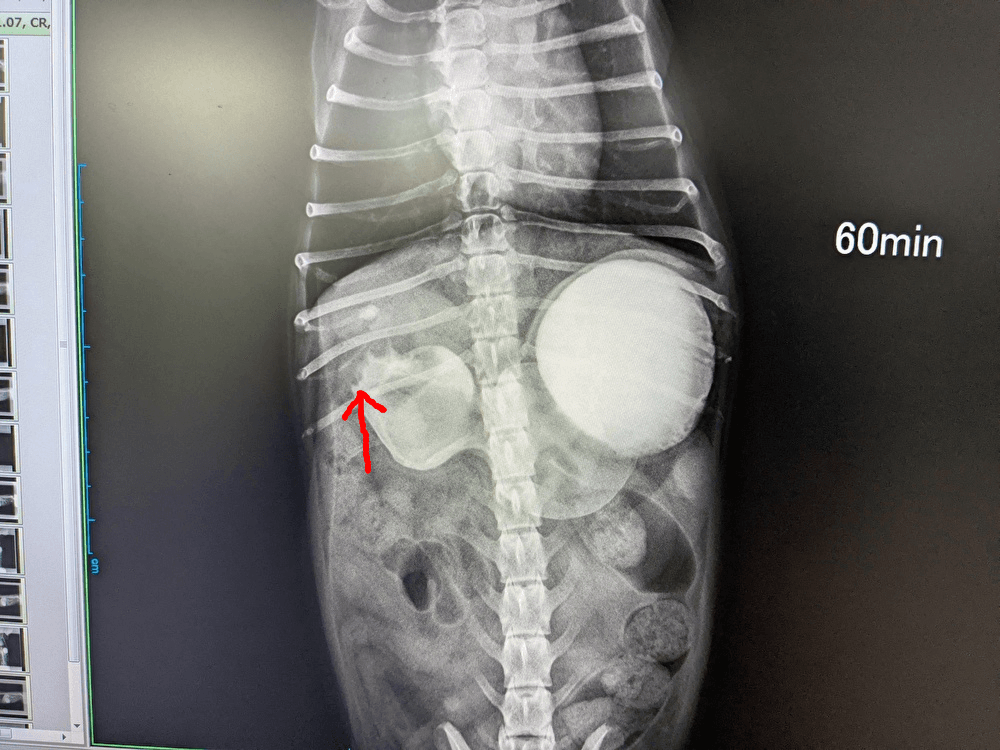

造影剤を飲んで1時間後のレントゲンです。矢印の部分が胃の幽門部です。

通常なら1時間も経てば液体はある程度小腸に流れていくはずですが、白い造影剤が赤矢印のところから流れず止まってしまっています。